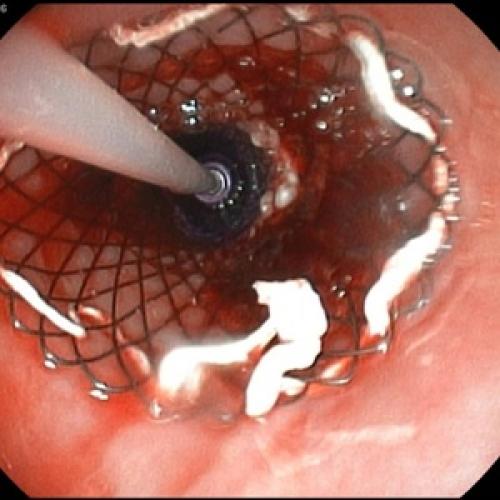

Отсутствие эффекта от проводимой анальгетической и спазмолитической терапии в течение 12-48 часов, быстро прогрессирующая желтуха, отсутствие желчи в ДПК при ЭГДС, признаки билиарной гипертензии по данным УЗИ свидетельствуют о стеноза терминального отдела холедоха (вклиненный конкремент БДС, папиллит). В этом случае показано проведение ЭПСТ. При остром панкреатите ЭПСТ производится без ЭРХПГ!

При скоплении в поджелудочной железе или окружающих ее органах воспалительной, содержащей токсические вещества, жидкости, проводят лапароскопию с целью санации (обеззараживания) патологического очага.

При наличии камней в желчных протоках, участков панкреонекроза, абсцессов, кист поджелудочной железы, скоплений жидкости в ней или окружающих органах пациенту показано хирургическое вмешательство, объем которого зависит от вида осложнений (некрэктомия, резекция (удаление части) поджелудочной железы, дренирование полости при помощи эндоскопа, марсупиализация кисты, лечебно-диагностическая лапароскопия и так далее).